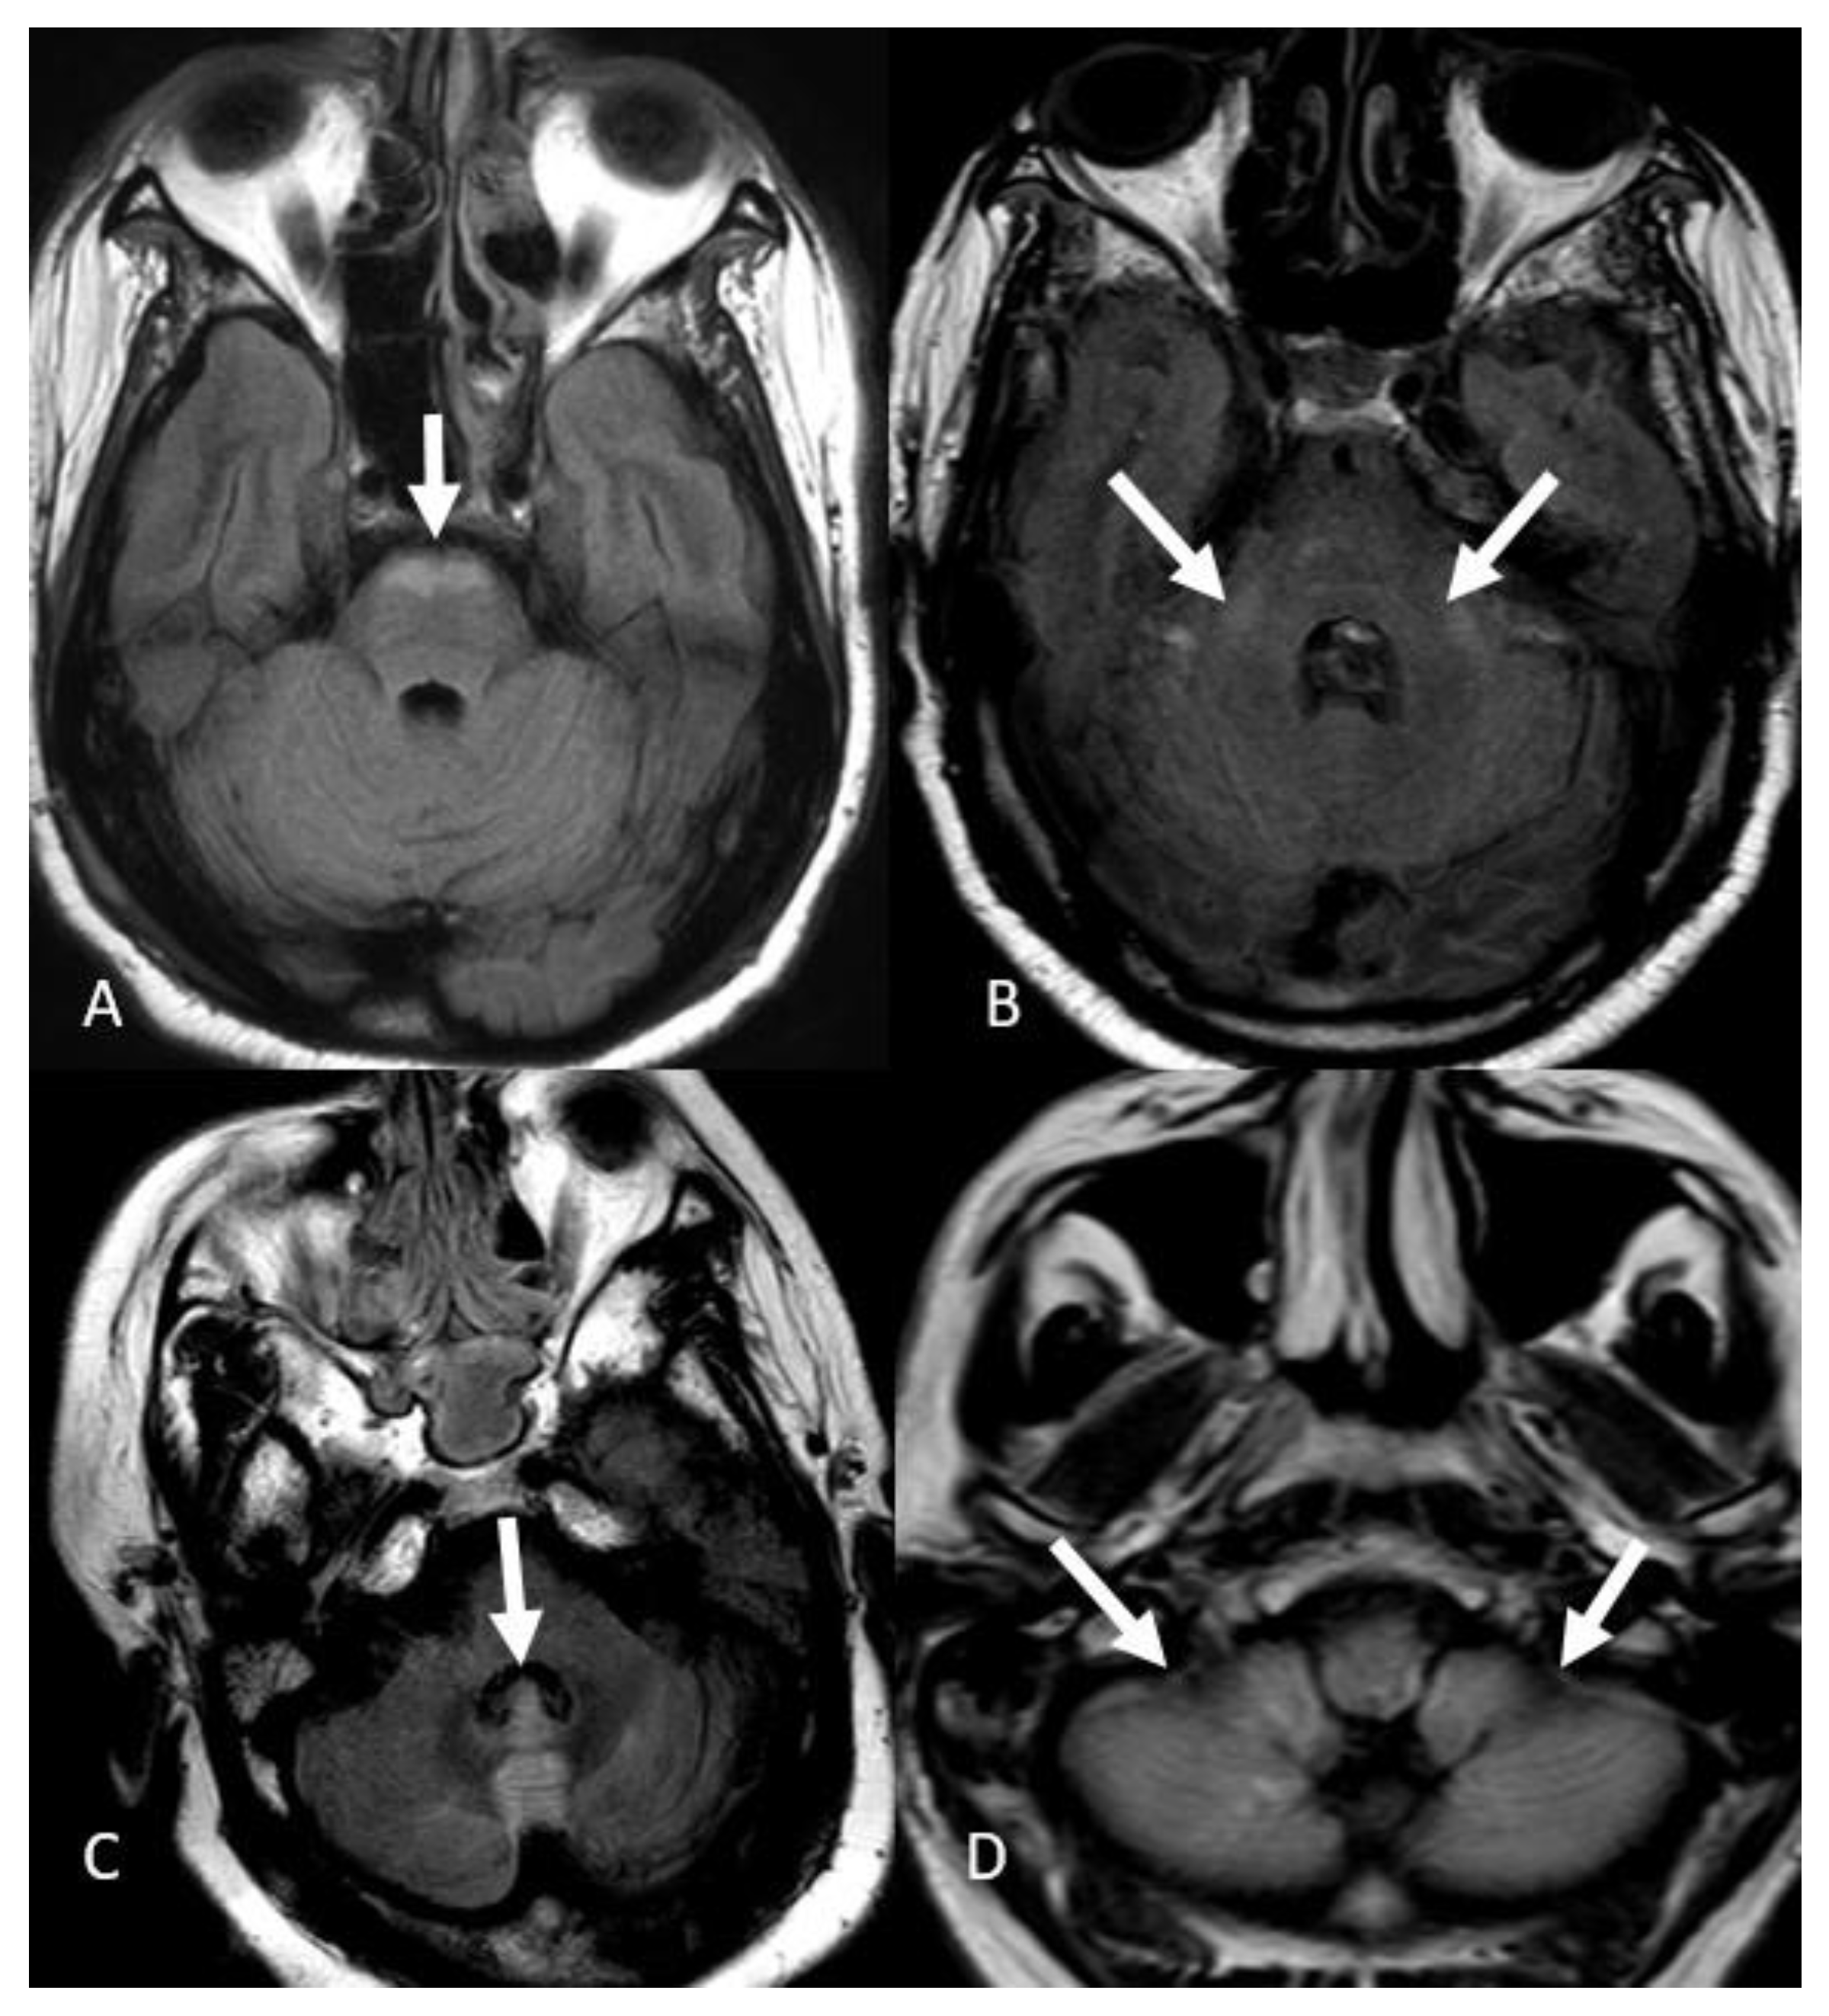

- Bulakbasi, N.; Kocaoglu, M. Central nervous system infections of herpesvirus family. Neuroimaging Clin. N. Am. 2008, 18, 53. [Google Scholar] [CrossRef] [PubMed]

- Oyanguren, B.; Sánchez, V.; González, F.J.; De Felipe, A.; Esteban, L.; López-Sendón, J.L.; Garcia-Barragán, N.; Millán, J.M.-S.; Masjuán, J.; Corral, I. Limbic encephalitis: A clinical-radiological comparison between herpetic and autoimmune etiologies. Eur. J. Neurol. 2013, 20, 1566–1570. [Google Scholar] [CrossRef] [PubMed]